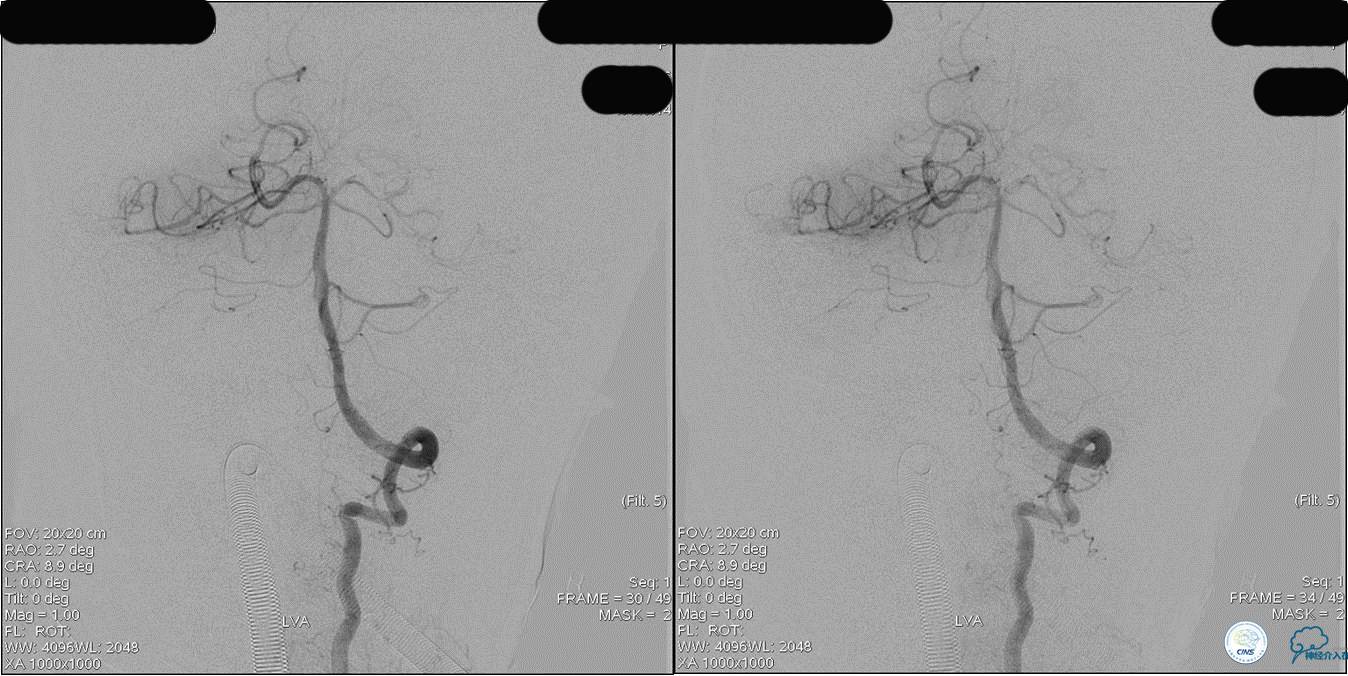

》DSA资料(第3次取栓后,发病10h)

》DSA资料(观察30min后,左椎造影)

★基底动脉尖端的血栓偏向哪侧,应该将Solitaire支架放入同侧的大脑后动脉,这样取栓的告捷率较高一些。